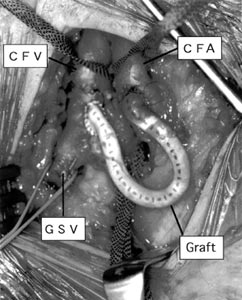

| Fig. 3 Operative photograph of the A-V fistula. CFA:

common femoral artery, CFV: common femoral vein, GSV: great saphenous vein |